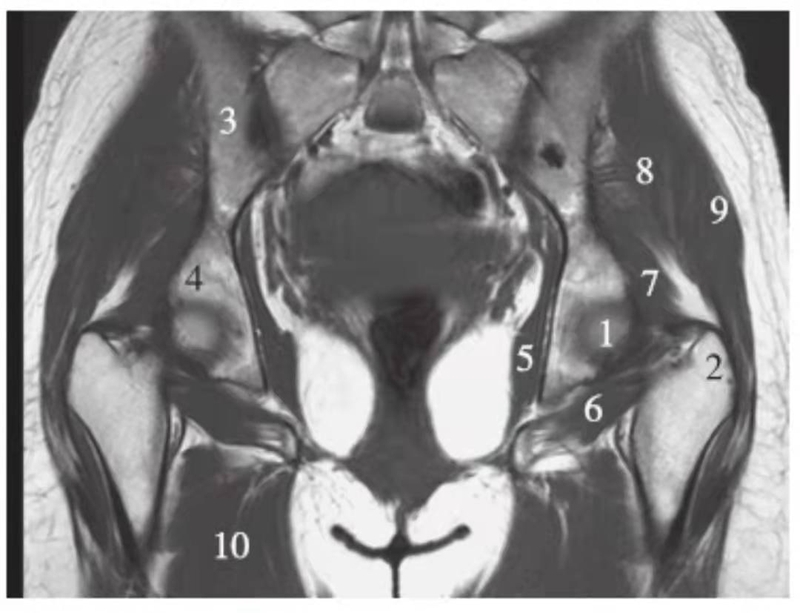

冠状位

正常髋关节经股骨头前缘层面T1WI像

1.股骨头;2.耻骨;3.髂骨;4.髂腰肌;5.内收肌群;6.臀小肌;7.臀中肌;8.关节囊及髂股韧带